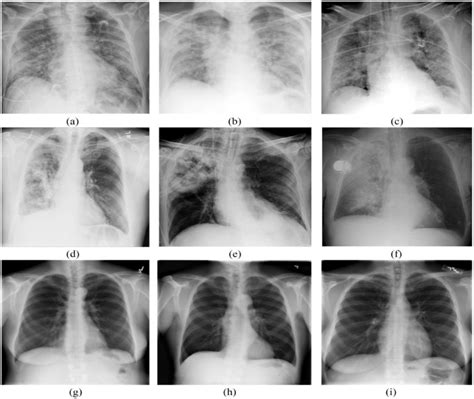

If you experience symptoms that could indicate either bronchitis or pneumonia, it is important to seek medical attention. A healthcare provider can perform a physical examination, order diagnostic tests such as a chest X-ray or blood tests, and provide an accurate diagnosis.